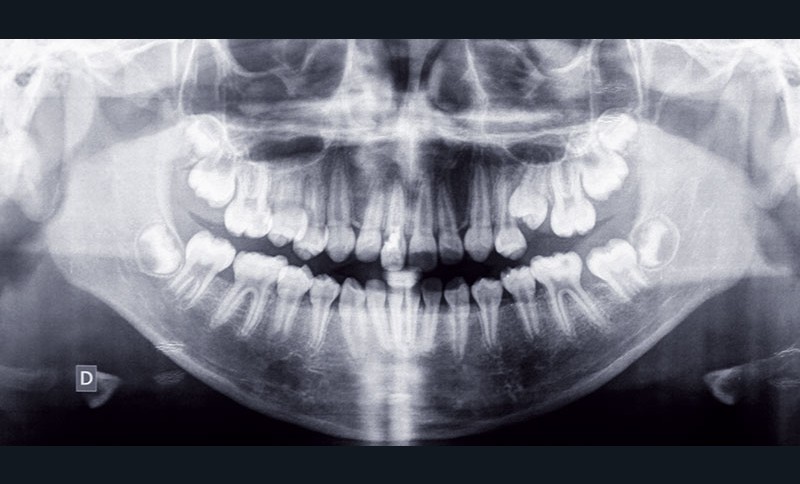

Situation clinique (fig. 1 à 9)

Orlhane B., 10 ans, est adressée à l’unité fonctionnelle d’orthodontie de l’hôpital Bretonneau par son dentiste suite à un traumatisme sur la 11. Le trait de fracture est infra-osseux et ne permet pas la réalisation d’une restauration prothétique de cette dent. Le praticien nous demande de réaliser une extrusion orthodontique afin d’égresser la dent sans que son parodonte suive le mouvement dentaire et d’augmenter ainsi l’espace biologique. La longueur radiculaire permet ce mouvement (rapport couronne/racine postextrusion inférieur à 1) et un traitement à l’hydroxyde de calcium est réalisé transitoirement durant le déplacement orthodontique. L’obturation finale sera réalisée une fois que les limites du trait de fracture seront supra gingivales et permettront la mise en place d’un champ opératoire étanche.

À l’examen clinique, Orlhane présente une classe I biproalvéolie aggravée par 11 fracturée et 25 enclavée et une classe II canine légère gauche. Cette malocclusion est associée à une classe II squelettique par promaxillie sur un schéma facial hyperdivergent. Il est décidé de ne pas traiter la biproalvéolie et la classe II squelettique modérées d’origine ethnique chez cette patiente.